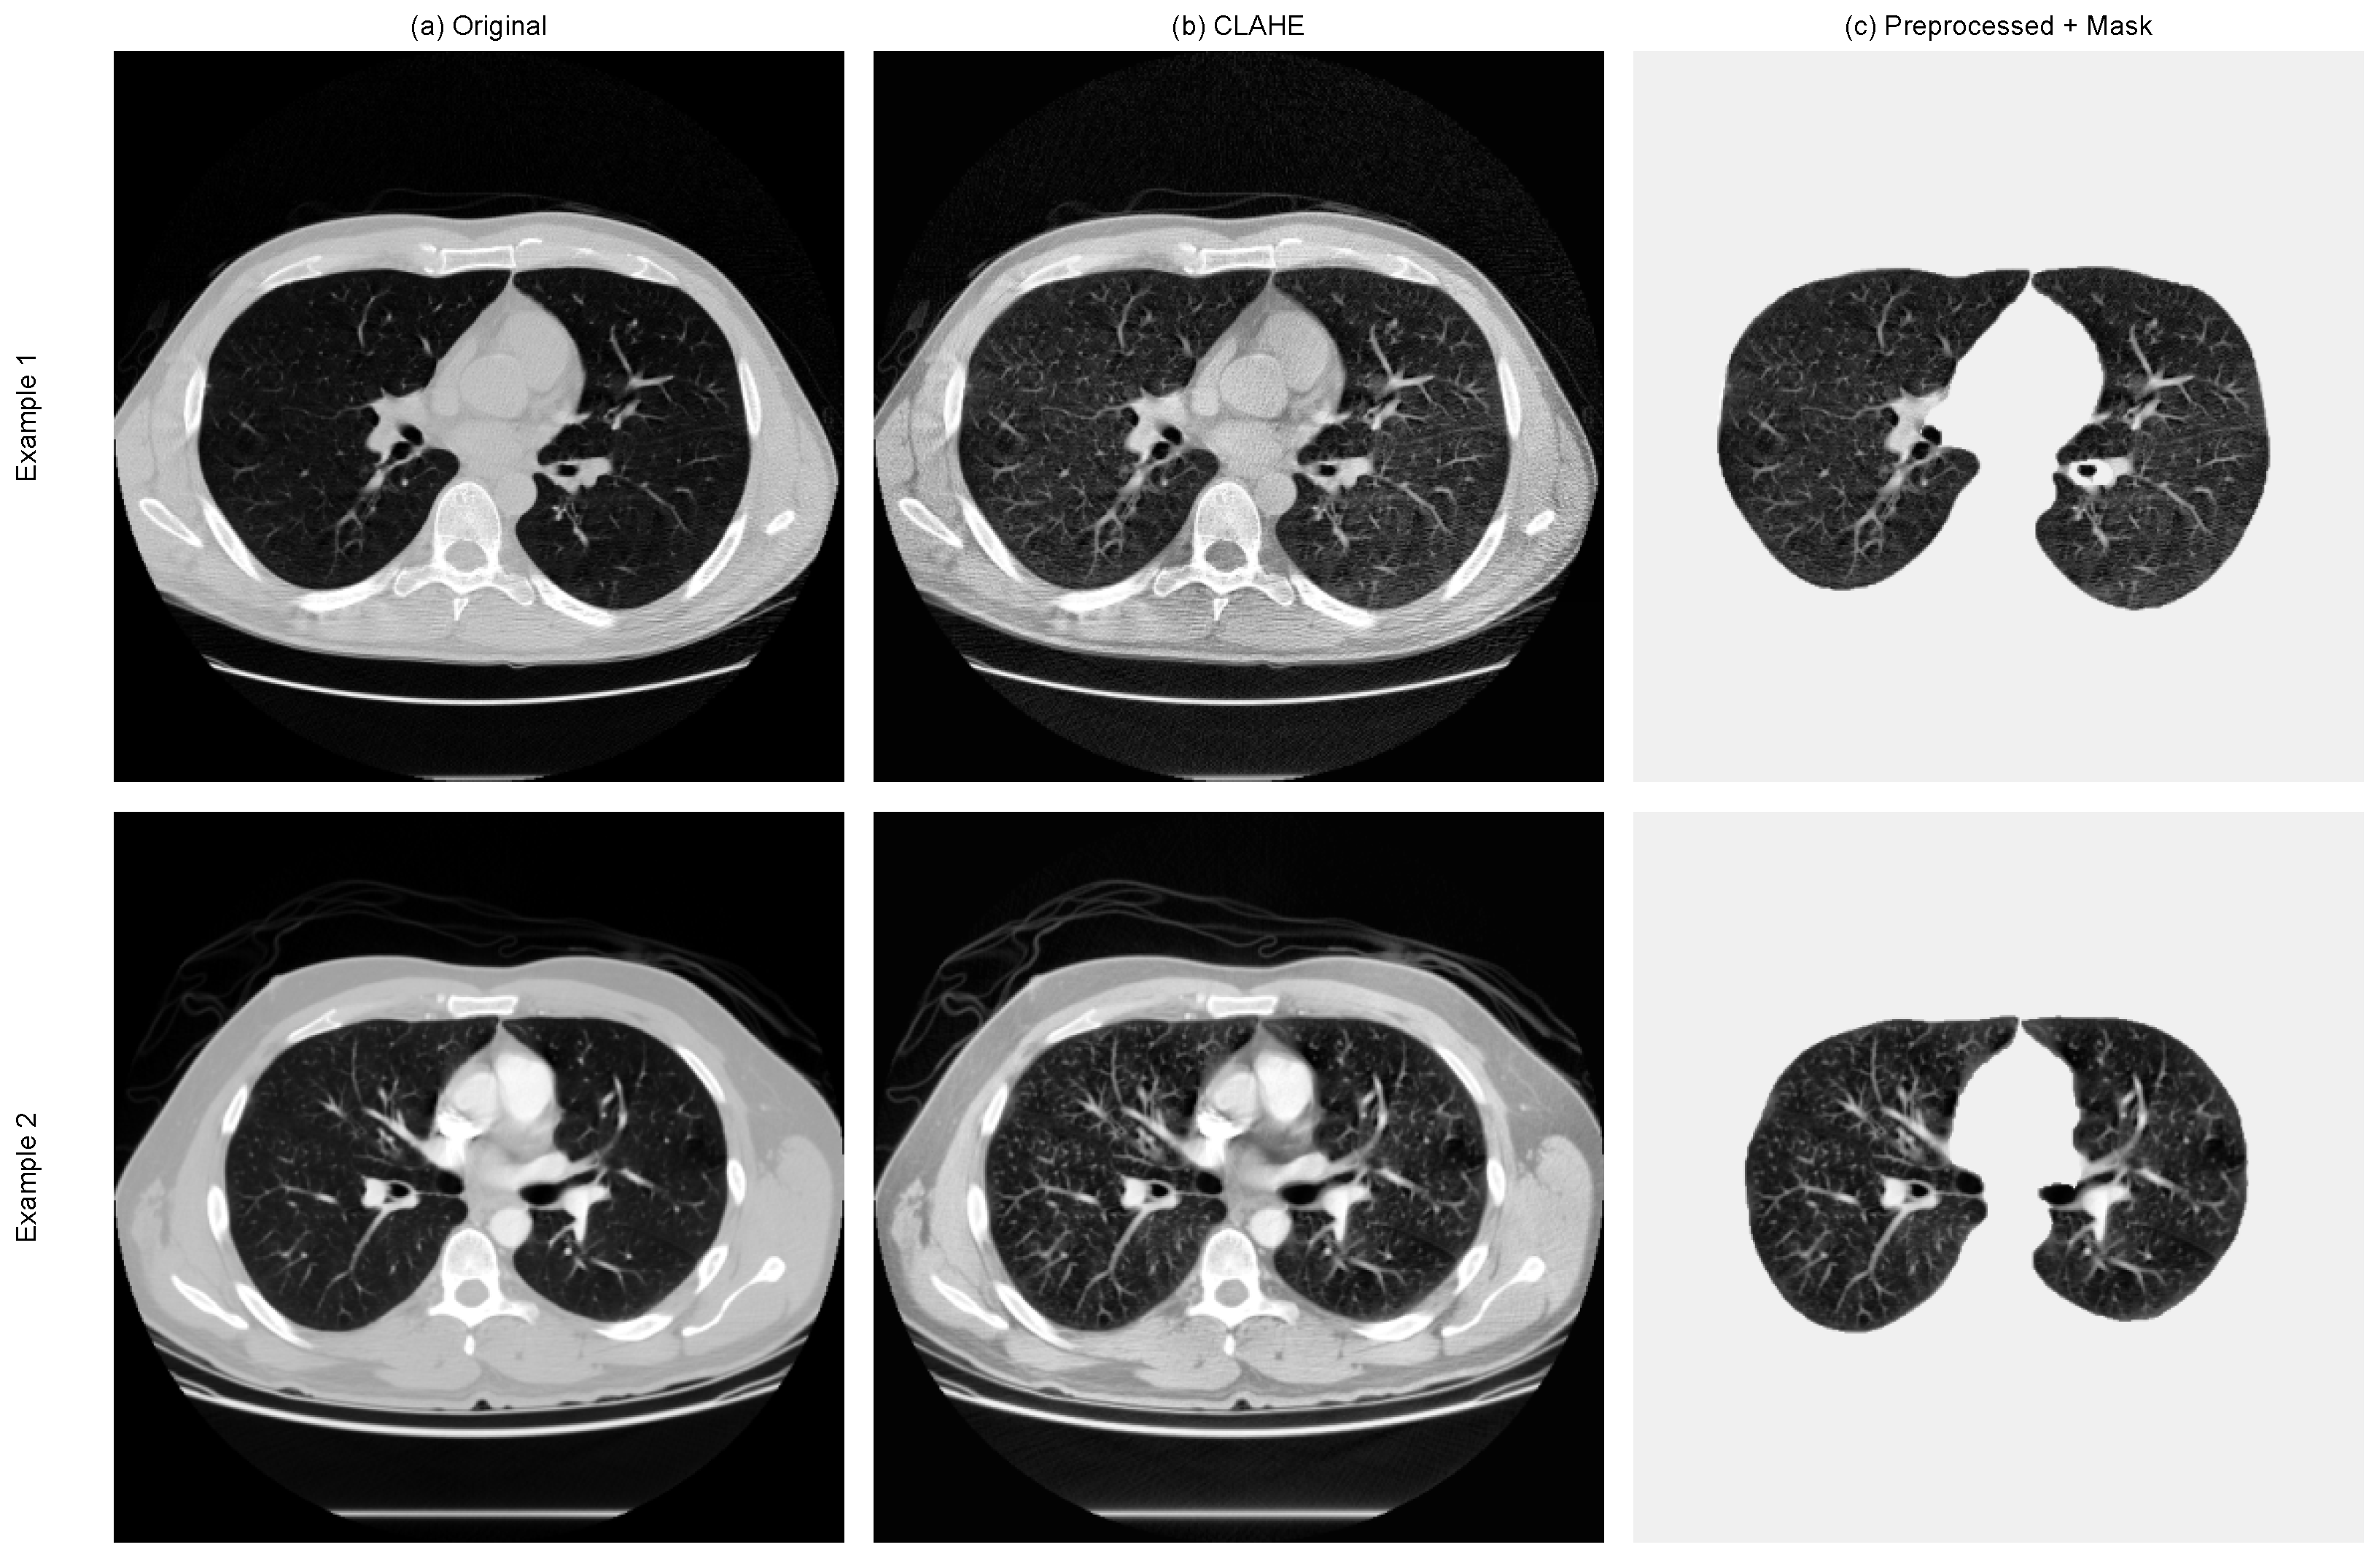

- A data pipeline tailored for LUNA16 (HU normalisation, CLAHE enhancement, lung masking, and slice-level packaging) for stable 2.5D inputs;

4.1. Image Enhancement and Quality Assessment

4.2. Preprocessing Visualisation